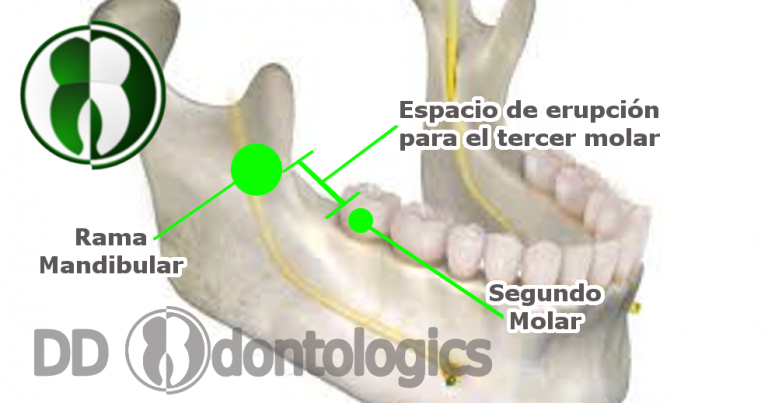

Desafortunadamente, un alto número de personas no desarrollan el espacio suficiente para que estas puedan erupcionar. Las muelas que presentan este problema por lo general, son los terceros molares inferiores, el espacio al que nos referimos es el que se encuentra entre el segundo molar (normalmente es el último que tenemos a la vista al final de la mandíbula) y la rama mandibular (el hueso cubierto de encía que marca el final de la mandíbula).

Esta falta de espacio, además de representar una barrera física para impedir que la muela erupcione, puede determinar también la posición en la que se orientaría ese diente durante su desarrollo, ya sea vertical (Normal), en diagonal u horizontalmente. El riesgo que se corre cuando se forman en posición horizontal o diagonal, es que pueden entrar en contacto con la raíz del segundo molar y esto puede ocasionar severos daños y dolores, inclusive hasta llegar a la necesidad de extraer ambos dientes.